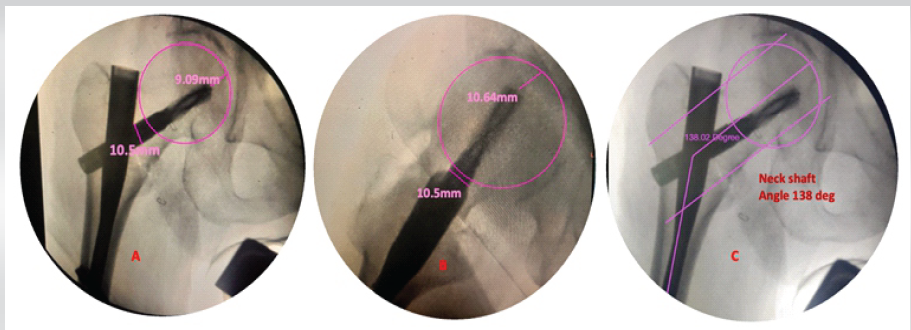

Post-operative radiographs were obtained, and they showed a neutral reduction, a Baumgaertner’s Tip Apex Distance (TAD) of 19.73 mm, the neck shaft angle was 138°, and Parker’s ratio was 38.9% (Figs. 2 and 3).

Figure 2: Intraoperative assessment of tip apex distance (TAD) (a) in anterior posterior 9.09 mm, 10.64 mm in lateral view (b), and total TAD = 19.73 mm (c) neck shaft angle 138°s.

Figure 3: (a) Parker’s ratio 38.9%, (b) Cleveland zone-center/center

The post-operative fracture gap was <1 mm, and Garden alignment index was good, and the center of the helical blade was placed in the Cleveland zone center–center. The reduction quality was good according to the Baumgaertner reduction quality criteria, and excellent according to the Chang reduction quality criteria, respectively.